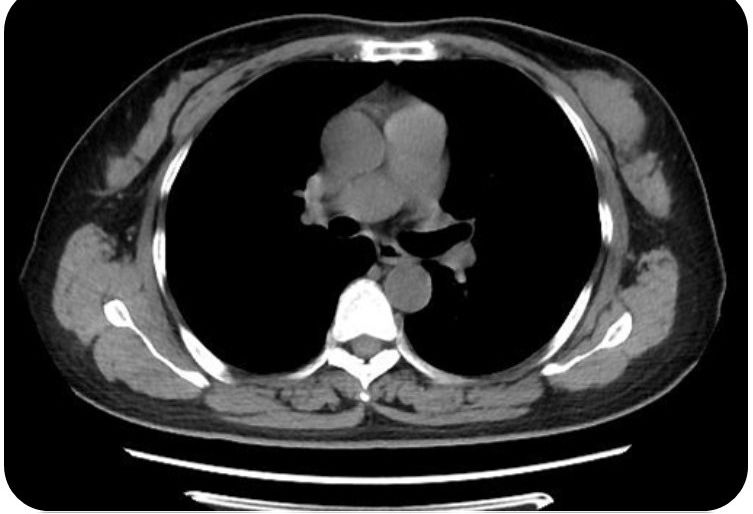

胸部CT:右肺上叶淡片状高密度影,考虑少许炎性病变,建议复查;双肺少许纤维灶;冠状动脉钙化。右肺上叶淡片状高密度影,考虑少许炎性病变,建议复查;双肺少许纤维灶;冠状动脉钙化。